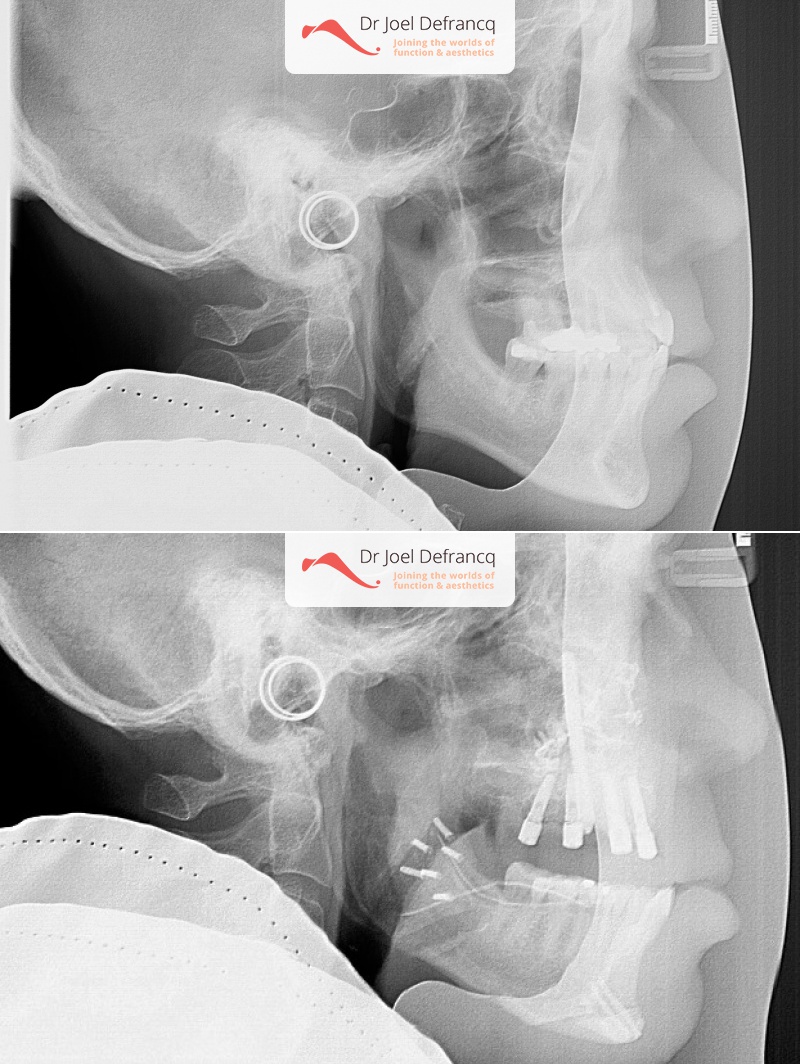

Kaakchirurgie

- Verlenging onderkaak (BSSO)

- Verlenging bovenkaak (Le Fort I)

- Vertikale verlenging bovenkaak (Le Fort I)